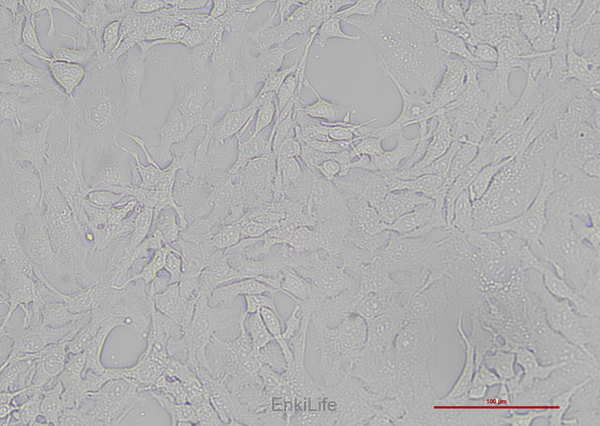

HCCC-9810 细胞源自一位女性肝胆管细胞癌患者,呈上皮细胞样。HCCC-9810细胞染色体模式数为71,但其染色体数目可以在22-117的范围内变动。HCCC-9810细胞倍增时间为20.4小时;细胞内AFP、CEA和CA19-9的分泌水平低,HCCC-9810细胞在裸鼠中的成瘤率为20%。

生长特性

贴壁细胞

细胞形态

上皮细胞样